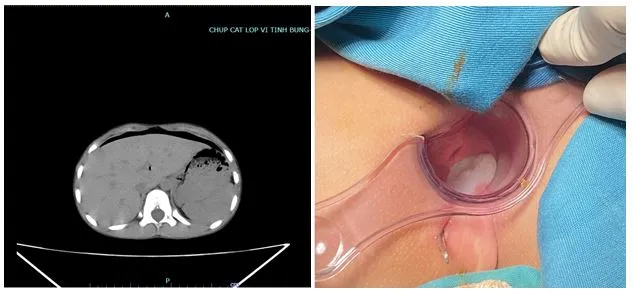

Qua thăm khám, các bác sĩ kết luận chiếc bút đâm vào tầng sinh môn, xuyên thủng trực tràng vào trong ổ bụng, gây viêm phúc mạc. Khả năng còn các tổn thương cơ quan khác trong ổ bụng.

Chiếc bút đâm vào tầng sinh môn, xuyên thủng trực tràng vào trong ổ bụng bệnh nhi. Ảnh: BVCC

Sau đó, các bác sĩ tiến hành phẫu thuật nội soi ổ bụng, thấy có vết thương đi ra mặt sau bàng quang, đâm thủng phúc mạc. Bệnh nhi được rửa ổ bụng, đặt dẫn lưu qua hậu môn.